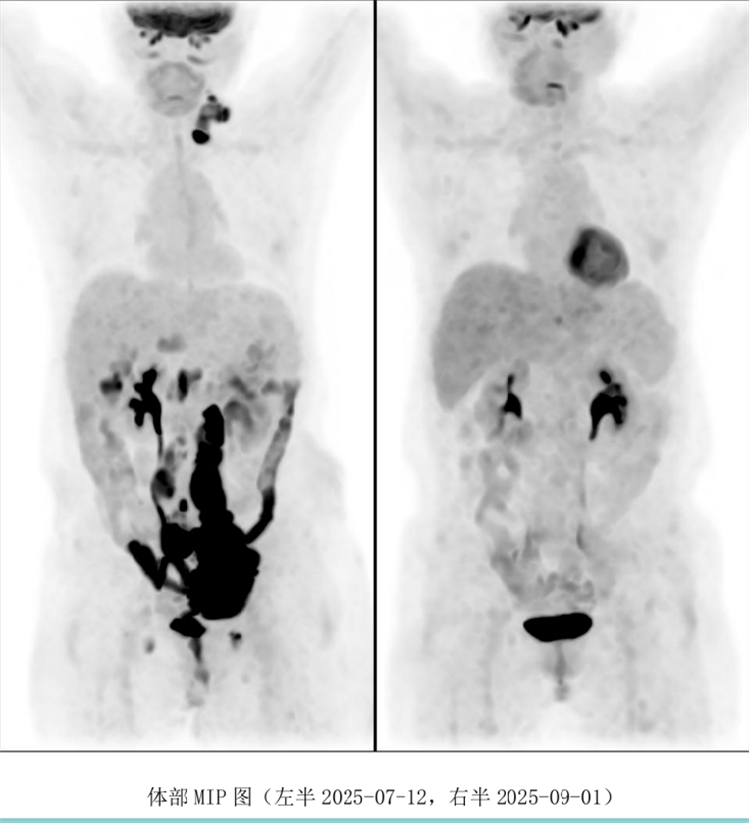

病例匯報環(huán)節(jié)由我院淋巴瘤科張薇醫(yī)生帶來了三例精彩紛呈的難治復(fù)發(fā)彌漫大B淋巴瘤CAR-T治療的病例。

病例過程跌宕起伏,從橋接治療到靶點(diǎn)的選擇,并發(fā)癥的處理都極具代表性。張醫(yī)生詳盡分享了患者在治療過程中的挑戰(zhàn)、決策依據(jù)以及CAR-T細(xì)胞治療后的驚人緩解與轉(zhuǎn)歸,充分展示了CAR-T技術(shù)為晚期患者帶來的突破性生存希望。